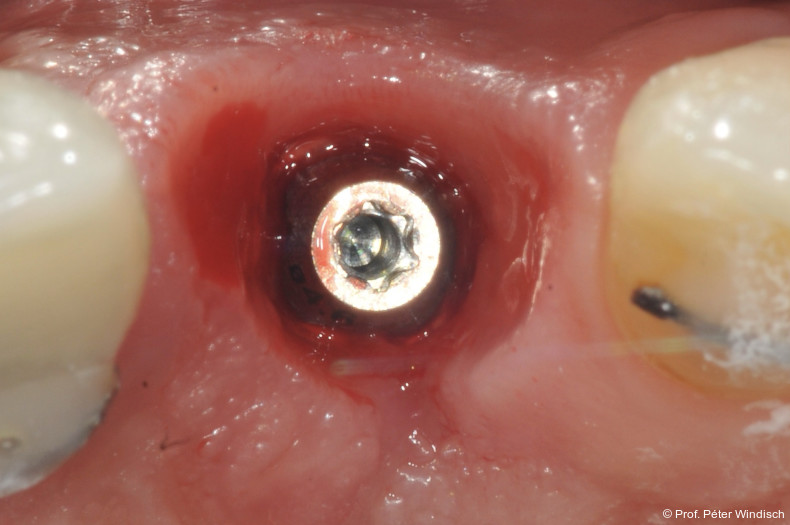

Die erste Säule der Behandlung („Clean“-Phase) bildete die submarginale Instrumentierung unterstützt durch das Reinigungsgel. Da eine rein mechanische Reinigung oft nicht ausreicht, um den Biofilm in den Mikrostrukturen der Implantatoberfläche vollständig zu entfernen, wurde nach dem Entfernen der Krone adjuvant das Reinigungsgel (Perisolv) eingesetzt.

Nach einer Einwirkzeit von mindestens 60 Sekunden (Abb. 6) wurde die Tasche und die Implantatoberfläche gründlich mit Titanküretten instrumentiert. Während der Instrumentierung wurde das Reinigungsgel mehrmals in die Tasche appliziert und 60 Sekunden einwirken gelassen (ca. fünf bis sechs Mal), jeweils gefolgt von weiteren Instrumentierungszyklen. Dies wurde so oft wiederholt, bis keine sichtbaren Konkremente mehr aus der Tasche kamen (Abb. 7).